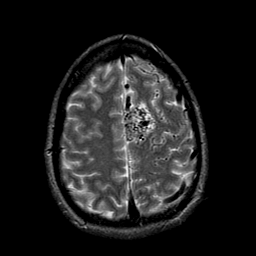

Vascular Malformation:T2-weighted MR #1 -- Slice #19

[Home][Help][Clinical] Slice 19